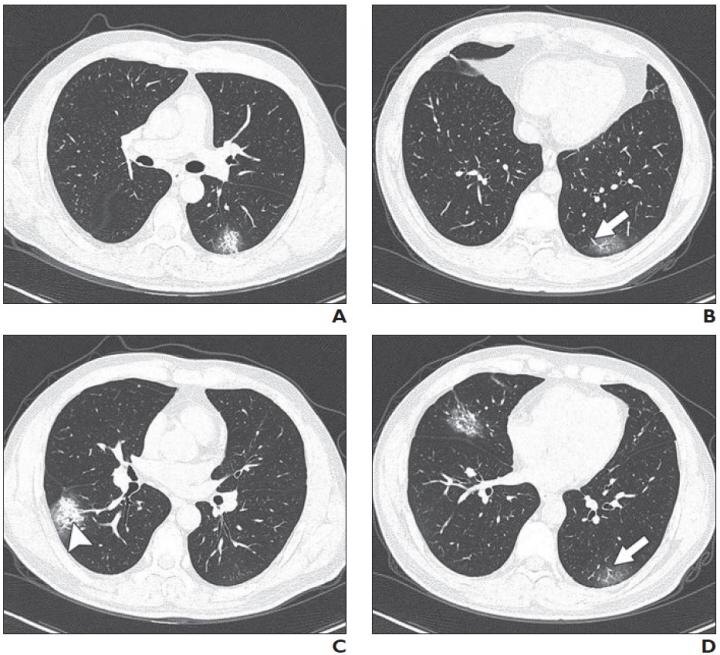

Пациент имел лихорадку (38°C) и кашель. КТ была выполнена в день поступления. На изображениях AD, CT показаны двусторонние мультифокальные помутнения по типу матового стекла (GGO) и смешанные повреждения, и консолидации. Тракционный бронхоэктаз (наконечник стрелки, C) и расширение сосудов (стрелка, B и D) также присутствуют. КТ вовлеченность 5 баллов.